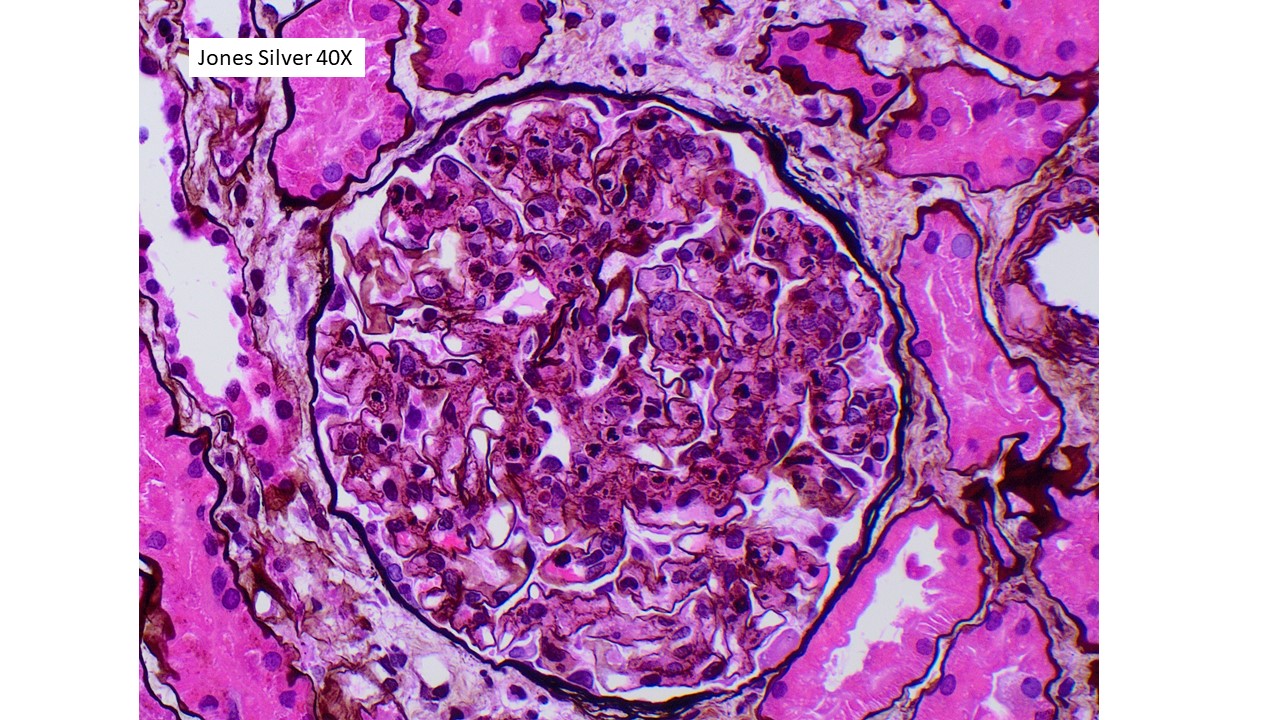

The findings in this patient’s renal biopsy are characteristic of acute postinfectious glomerulonephritis. Light microscopy shows a diffuse and global glomerular exudative process. Glomerular hypercellularity is primarily due to an influx of leukocytes (especially neutrophils, but also admixed monocytes), but which also includes a component of intrinsic renal cell proliferation (e.g. podocytes and mesangial cells), as well as endothelial cell swelling. Jones silver stain highlights the capillary basement membranes within glomerular tufts, and leukocytes and swollen endothelial cells can be seen filling and distend the glomerular capillary lumina. Immunofluorescence staining in this case showed predominant staining for C3 (3+ intensity), with lesser staining for IgG (1+ intensity) in a coarse chunky granular pattern that is mainly seen along capillary walls, often described as “lumpy bumpy” or “starry sky”, indicating a predominantly subepithelial deposition of immunoreactants. Other immunoreactants were negative. Electron microscopy in this case was classic of postinfectious glomerulonephritis, with large “hump-like” electron dense deposits seen in the subepithelial location.